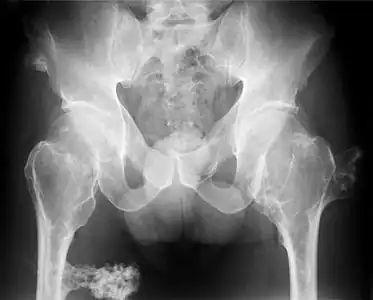

Hereditary multiple osteochondromas (HMO), also known as hereditary multiple exostoses, is a disorder characterized by the development of multiple benign osteocartilaginous masses (exostoses) in relation to the ends of long bones of the lower limbs such as the femurs and tibias and of the upper limbs such as the humeri and forearm bones. They are also known as osteochondromas. Additional sites of occurrence include on flat bones such as the pelvic bone and scapula. The distribution and number of these exostoses show a wide diversity among affected individuals. Exostoses usually present during childhood. The vast majority of affected individuals become clinically manifest by the time they reach adolescence.[1][2] A small percentage of affected individuals are at risk for development of malignant transformation namely sarcomas. The incidence of hereditary multiple exostoses is around 1 in 50,000 individuals.[3] Hereditary multiple osteochondromas is the preferred term used by the World Health Organization.

A noticeable lump in relation to an extremity may be the first presenting symptom. Multiple deformities can arise, namely coronal plane deformities around the knees, ankles, shoulders, elbows, and wrists. For example, genu valgum (knock knees), ankle valgus, ulnar bowing and shortening, and radial head subluxation are encountered. The majority of affected individuals have clinically manifest osteochondromas around the knee. Forearm involvement in HMO is considerable.[1][4] Furthermore, short stature may occur and is generally disproportionate. Such manifestations usually result from disruption of physeal growth especially that osteochondromas typically arise at the metaphyseal ends of long bones in close proximity to the physis.[1][4] Intra-articular osteochondromas of the hip can induce limitation of range of motion, joint pain and acetabular dysplasia.[2] Likewise joint pain at other locations and neurovascular compression can occur. Furthermore, functional disability in regard to activities of daily living can be a presenting feature. Spinal deformity pain or neurological compromise should arouse suspicion of involvement of the vertebrae.[3]

It is characterized by the growth of cartilage-capped benign bone tumours around areas of active bone growth, particularly the metaphysis of the long bones. Typically five or six exostoses are found in upper and lower limbs. Most common locations are:[15]

The diagnosis of HMO is based upon establishing an accurate correlation between the above-mentioned clinical features and the characteristic radiographic features. Family history can provide an important clue to the diagnosis. This is supplemented by testing for the two genes in which pathogenic variants are known to cause HMO namely EXT1 and EXT2. A combination of sequence analysis and deletion analysis of the entire coding regions of both EXT1 and EXT2 detects pathogenic variants in 70–95% of affected individuals.[3][4] The hallmark of radiographic diagnosis is the presence of osteochondromas at the metaphyseal ends of long bones in which the cortex and medulla of the osteochondroma represent a continuous extension of the host bone. This is readily demonstrable in radiographs of the knees.[3][1]